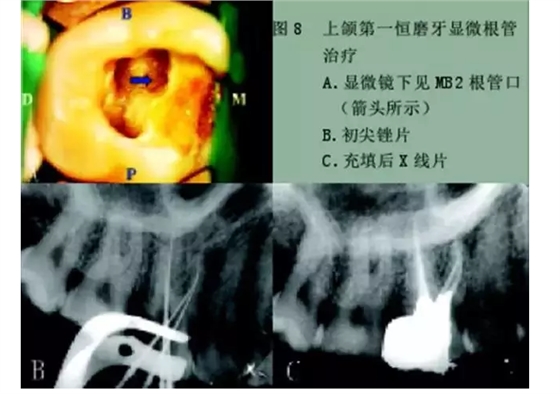

1)尋找遺漏根管

2)根管系統(tǒng)的解剖形態(tài)是極其復(fù)雜的。牙髓病學(xué)教材中常常提到磨牙有三個(gè)根管,前磨牙兩個(gè)根管,前牙一個(gè)根管。實(shí)際上,根管系統(tǒng)并不是如此可預(yù)知的,而是常常存在許多解剖變異。根管系統(tǒng)的解剖形態(tài)學(xué)研究發(fā)現(xiàn):幾乎50%磨牙中(上頜和下頜)有第四根管存在,30%以上的前磨牙有第三根管,接近25%的前牙有雙根管。

在傳統(tǒng)的根管治療中,開髓后往往只是依靠術(shù)者的視覺和經(jīng)驗(yàn)去尋找根管,所以常常存在遺漏根管的可能,從而導(dǎo)致根管治療的失敗。研究發(fā)現(xiàn),X線片上顯示根管充填滿意的患牙仍有癥狀的主要原因是有遺漏的根管未治療。

所以對(duì)于經(jīng)過完善根管治療后的牙,如果出現(xiàn)持續(xù)疼痛,首先應(yīng)該考慮可能有遺漏根管的可能。

手術(shù)顯微鏡是用于尋找隱藏或遺漏的根管最重要的工具。因?yàn)槭中g(shù)顯微鏡能夠幫助醫(yī)生觀察到肉眼或普通放大鏡無法分辨的根管口和微小病損。在手術(shù)顯微鏡下,利用高倍數(shù)(16~24倍)的放大作用以及理想的照明條件,仔細(xì)檢查患牙的髓室底,許多細(xì)微的解剖結(jié)構(gòu)能容易被發(fā)現(xiàn)。

為了光線能充分進(jìn)入髓腔,髓室頂應(yīng)完全揭去,開髓口的形態(tài)應(yīng)根據(jù)具體牙位進(jìn)行適當(dāng)修改,使得所有根管口都能夠充分暴露。同時(shí),對(duì)髓底進(jìn)行美藍(lán)染色也有助于根管口和微小病損的識(shí)別。